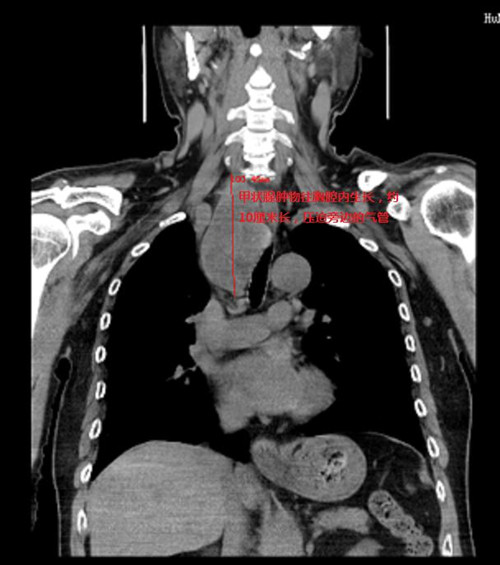

66岁的周嗲嗲家住马王堆,因气促咳嗽在湖南省人民医院呼吸五科住院,胸部CT检查发现在右肺下叶有一个约鹌鹑蛋大小结节,同时在纵膈发现一巨大肿物压迫气管引起狭窄,经胸外科会诊,右肺下叶结节肺癌的可能性非常大,纵膈肿物是颈部甲状腺肿瘤往胸腔内长压迫气管,两个问题都要手术治疗。

恰逢2021年12月31日胸外二科在马王堆院区新开科,周嗲嗲从呼吸五科转到胸外二科。传统的胸骨后甲状腺肿物切除有可能要正中劈开胸骨,创伤非常大。为了尽可能减少手术对病人带来的创伤,周亚夫主任与乳甲外科、麻醉科、手术室开展术前讨论,制定最微创的手术方案。